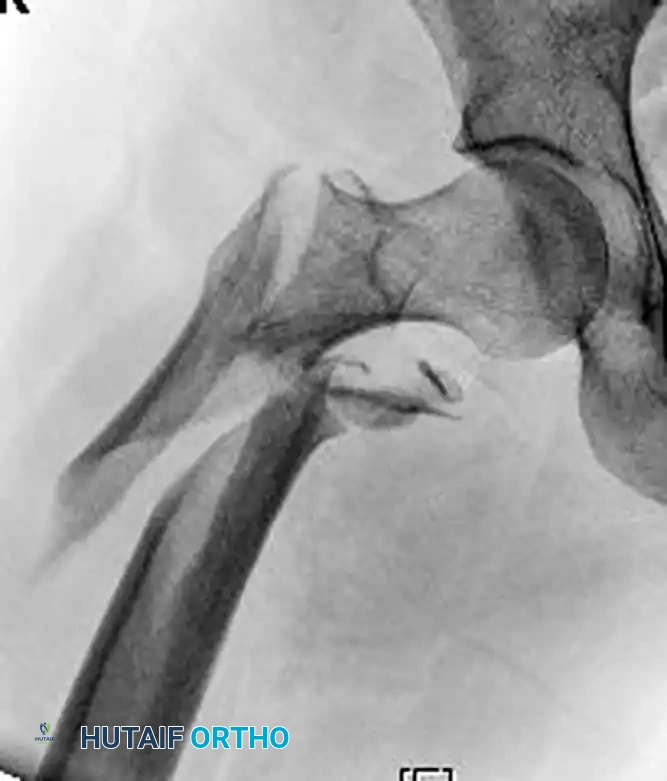

To correct sagittal and coronal plane deformities, utilize a Cobb elevator and a ball spike pusher. The elevator can be used to lever the proximal fragment out of flexion, while the ball spike pusher controls abduction and rotation.

Figure C: Intraoperative AP fluoroscopic image showing the elevator and ball spike pusher actively correcting the coronal deformity.

Figure D: Intraoperative lateral fluoroscopic image demonstrating the correction of the sagittal plane deformity using the same reduction aids.